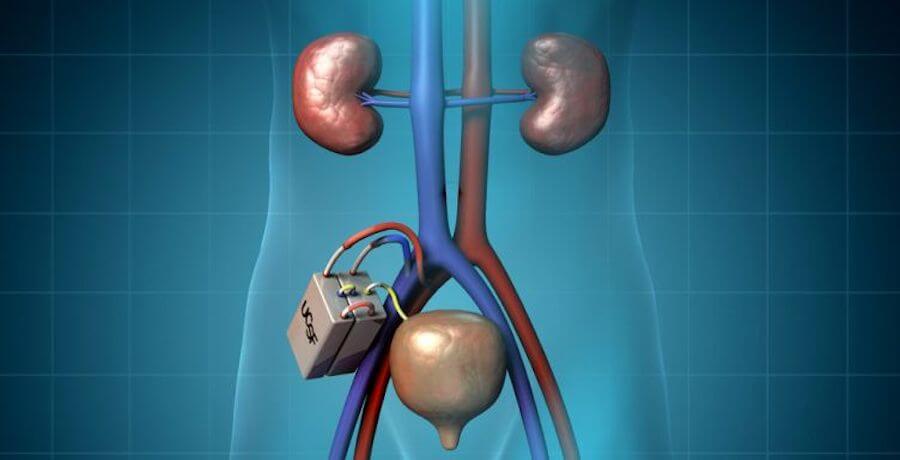

O protótipo do primeiro rim artificial biônico tem como data de lançamento o ano de 2017.

Anunciando por uma equipe de cientistas da universidade de Califórnia, São Francisco, o projeto tem como fim acabar com as filas de espera e libertar os doentes da hemodialise.

O rim artificial biônico é composto por filtros de silício e células vivas. Funciona em conjunto com o coração humano e múltiplos microprocessadores para filtrar o nosso sangue.

O protótipo otimiza a pressão arterial e equilibra os níveis de sódio e potássio presentes no corpo do utente.

A expectativa do mercado para o rim biônico e de 2 anos, segundo o pesquisador principal, Victor Gura.